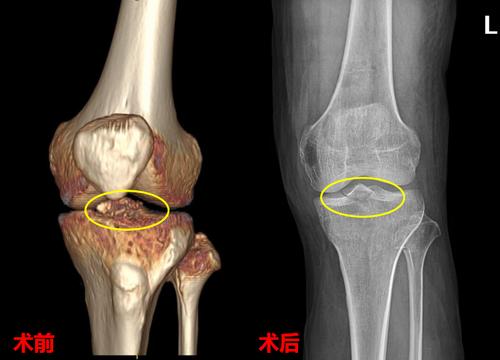

肿胀,活动受限,在外院做膝关节x线检查发现是左侧胫骨髁间棘骨折

胫骨髁间棘撕脱骨折.ppt

髁间棘骨折

胫骨髁间棘骨折图片

胫骨髁间棘撕脱性骨折

胫骨髁间嵴骨折手术

胫骨髁间隆突骨折